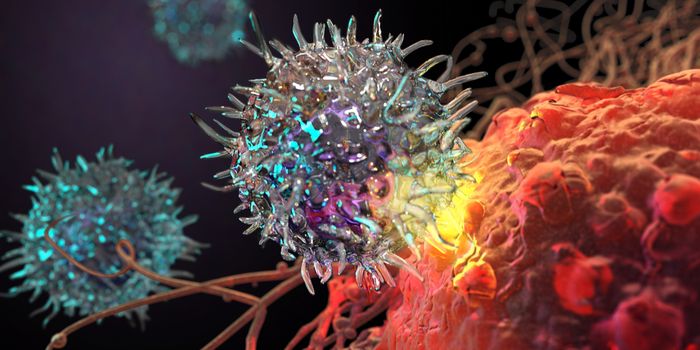

FEB 22, 2024ImmunologyThe US Food and Drug Administration (FDA) recently approved a tumor-infiltrating lymphocyte (TIL) therapy referred to as ...

FEB 15, 2024ImmunologyThere are various ways to treat cancer. The gold standard has been chemotherapy for over 50-years. However, treatment wi ...

JAN 11, 2024ImmunologyImmunotherapy has transformed the way we treat cancer patients. An alternative approach to chemotherapy, immunotherapy e ...